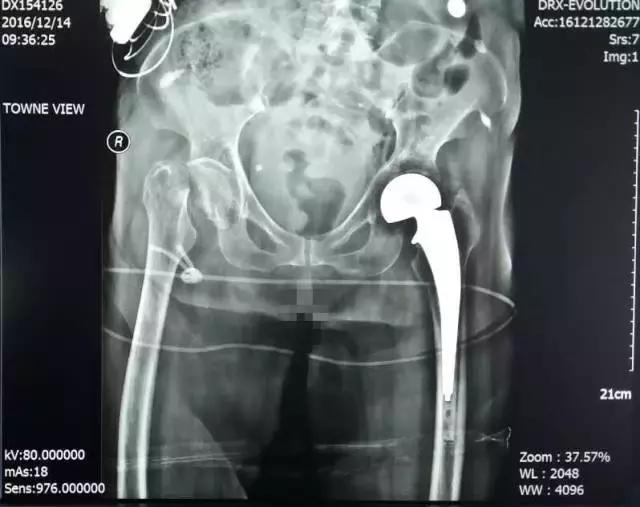

程XX术前X线

患者程XX,女,87岁,患者因跌倒致右髋部疼痛,活动受限5天就诊。

入院诊断:1、右侧股骨颈骨折;2、骨质疏松(重度);3、腰椎退行性骨关节病;4、颈椎病;5、双侧膝关节骨关节病;6、左髋关节置换术后;7、白内障;8、消化道溃疡。

诊疗措施:患者因右侧股骨颈骨折伴重度骨质疏松,双膝关节骨性关节病行右侧人工股骨头置换术。术前有重症肺炎,慢性阻塞性肺病,慢性肺源性心脏病等并发症。术中成功置换股骨头,复位后见关节稳定,匹配及活动度良好,术后我科医护人员密切观察患者各项生命体征,积极治疗护理,最终患者恢复了生活自理能力。